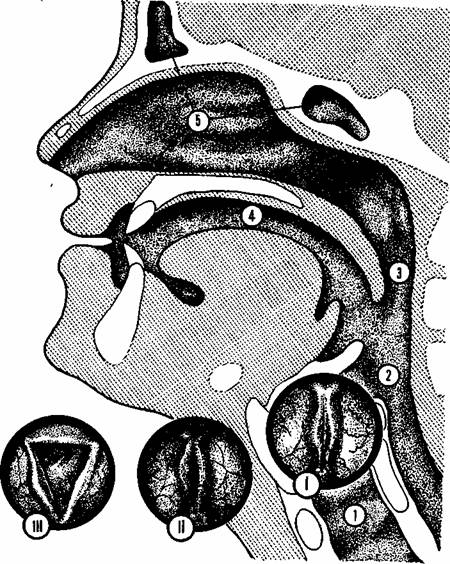

В механизме голосообразования принимают активное участие диафрагма, легкие, бронхи, трахея, гортань, глотка, носоглотка, полость носа (рис. 42). Органом голосообразования является гортань. Когда мы говорим, расположенные в гортани голосовые складки смыкаются (рис. 42, положение I). Выдыхаемый воздух давит на них, заставляя колебаться. Мышцы гортани, сокращаясь в разных направлениях, обеспечивают движение голосовых складок.

В результате возникает колебание частиц воздуха, находящегося над складками. Эти колебания, передаваясь в окружающую среду, воспринимаются как звуки голоса. Когда мы молчим, голосовые складки расходятся, образуя голосовую щель в виде равнобедренного треугольника (рис. 42, положение II).

При шепоте голосовые складки сомкнуты не полностью и меньше трутся друг о друга (рис. 42, положение III). Поэтому при необходимости щадить голосообразующий аппарат рекомендуется говорить шепотом.

Рис. 42. Голосоооразующий аппарат: 1 — гортань; 2 — глотка; 3 — носоглотка; 4 — полость рта; 5 — полость носа и придаточные пазухи